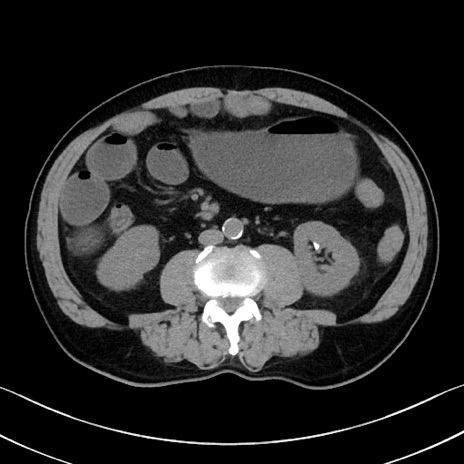

症例35(横断像)

【症例】70歳代 男性

【主訴】腹部膨満、嘔吐

【現病歴】昨日より腹部膨満感出現。本日増悪し、仙痛出現。嘔吐あり、受診。

【既往歴】糖尿病、胆摘後

【身体所見】BP 149/80mmHg、HR 74/min、BT 35.9℃、腹部:膨満、軟、圧痛なし。腸雑音減弱あり。上腹部正中切開瘢痕あり。

【データ】WBC 13500、CRP 1.72